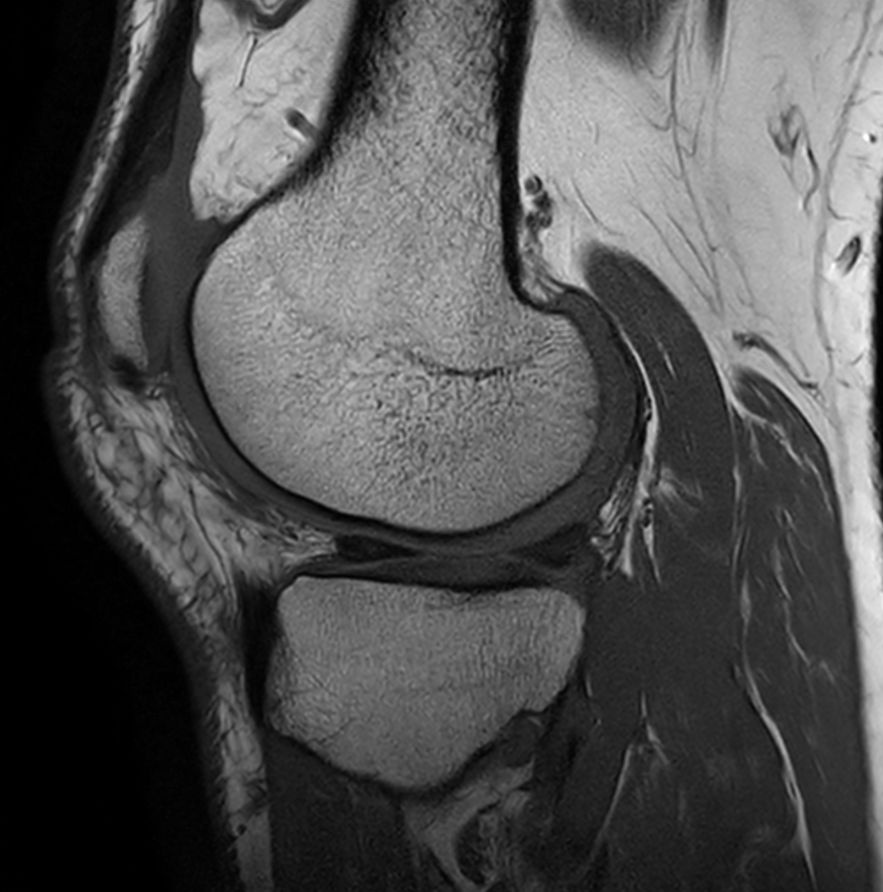

Sagittal T1w TSE - Compressed SENSE